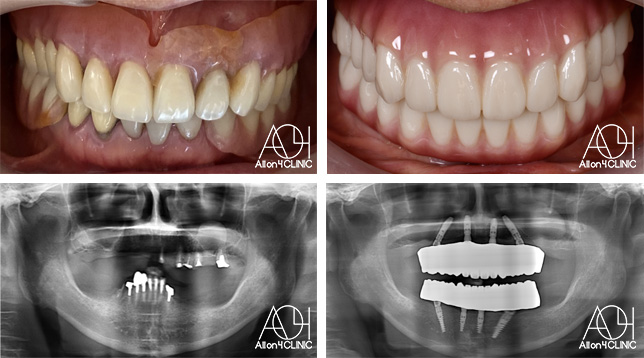

男性 / 56歳

仕事が忙しく歯には全く関心が無く、とうとう食事が困難になり治療を受ける事を決意。

治療詳細:ガイデッドサージェリーにてインプラント埋入。極めて骨量が少ないためザイゴマインプラントにて治療。

費用:¥7,920,000(税込)『モニター割引適用』

リスク:治療後の口腔管理が不適切な場合、埋入したインプラント周囲に感染・炎症を起こし、脱落する可能性がございます。